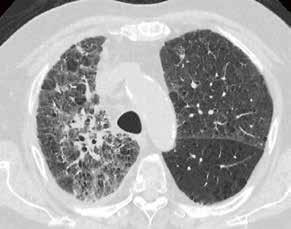

Fall 3:

Thorax-CT im Rahmen einer Lungenkrebsfrüherkennungsstudie. Die Voruntersuchung lag als externe kontrastmittelgestützte Thorax-CT vor. Bei der dosisoptimierten Low-Dose-CT liegt die Strahlenexposition nur noch im Bereich von zwei konventionellen Röntgenaufnahmen des Thorax, die Bildqualität ist für die Fragestellung nach Herdbefunden aber dennoch eindeutig ausreichend, selbst interstitielle Lungenveränderungen lassen sich hier noch beurteilen.

Prof. Dr. med. Johannes Weßling Zentrum für Radiologie, Neuroradiologie und Nuklearmedizin Abb. 3 a: kontrastmittelgestützte Thorax-CT, externe Untersuchung; DLP 216,0 mGy × cm / 3,9 mSv. Abb. 3 b: dosisoptimierte Low-Dose-Thorax-CT, Canon Aquilion Prime SP, Rekonstruktion: AiCE; DLP 13,9 mGy × cm / 0,25 mSv.